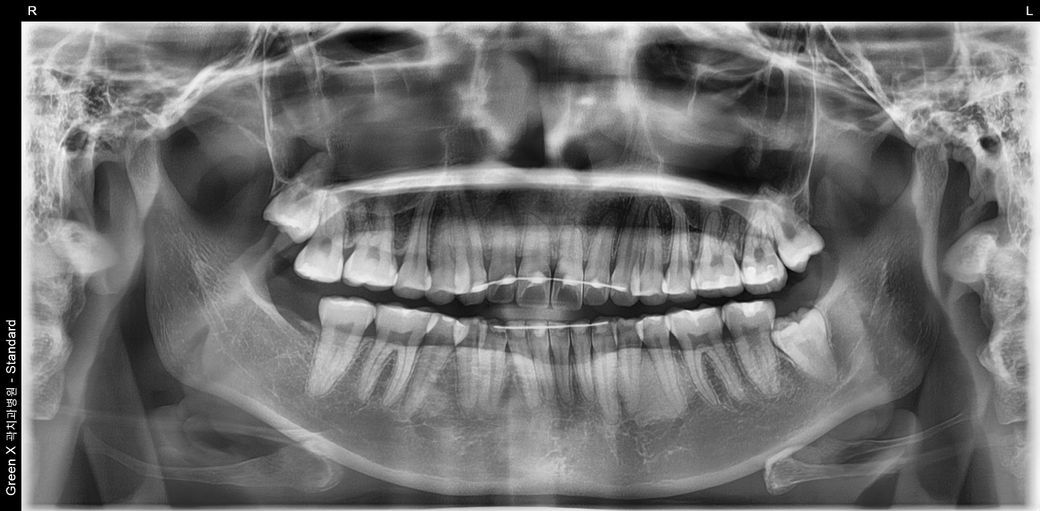

제 왼쪽 아래 매복사랑니 신경과 많이 가까운가요? 발치 시 신경손상의 가능성이 큰 편인지 궁금합니다

왼쪽 아래 매복사랑니가 신경과 가까워서 발치 시 신경손상 가능성이 좀 있다고 말씀하시던데

제 왼쪽 매복사랑니가 신경이랑 얼마나 가까운 건지,

신경 손상의 가능성이 다른 치아에 비해 정말 비교적 큰 편인지... 알고 싶습니다.

왼쪽 아래 사랑니가 깊이 매복되어 밑으로 지나가는 신경관과 사랑니 뿌리가 맞닿아 있습니다. 이런 경우 사랑니 발치후 입술이나 혀 감각이상이 오는 신경관 손상이 올 확률이 높습니다. 그렇지만 매복 사랑니 그냥두면 바로옆 어금니 상하게 하니 위험부담 앉고 발치하는 것을 추천합니다. 신경관 손상 안 올 수도 있습니다.

사진으로 봤을 경우에는 매우 깊이 있는 사랑니 이며 발치를 하면서 신경손상이 될 가능성이 높아 보입니다.

파노 상으로는 가까워 보이지만 CT상으로 보면 사랑니와 신경관과의 거리가 잇어 보입니다. 크게 걱정은 하지 않으셔도 될것같습니다. 단, 대학병원에서 발치를 하시는게 좋을것같습니다.